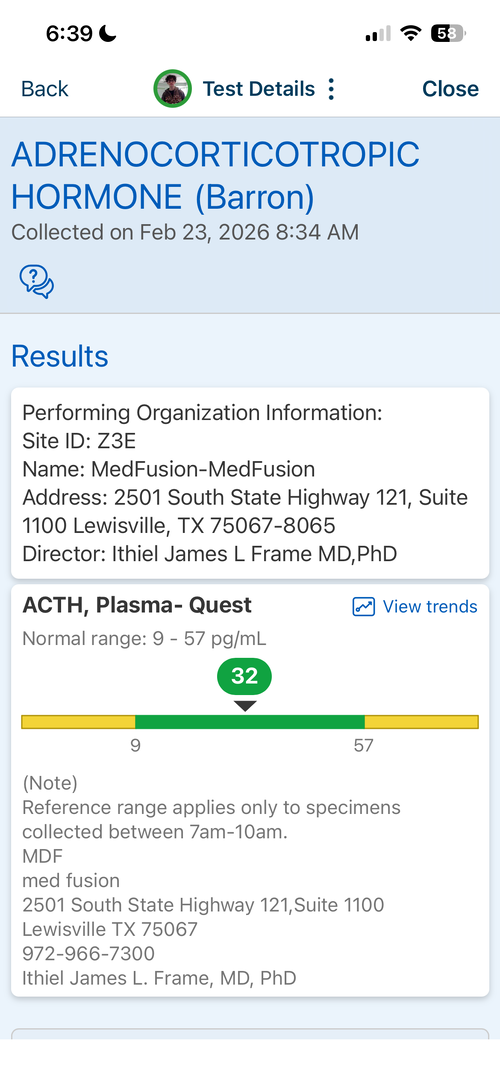

16.6 yr old male at 5'11.1" in height currently. Father is 6'1.5" and Mother is 5'8". I have images of my growth chart along with an X-Ray of my wrist attached. I also attached recent bloodwork tests of TESTOSTERONE, IGF-1 and Cortisol.